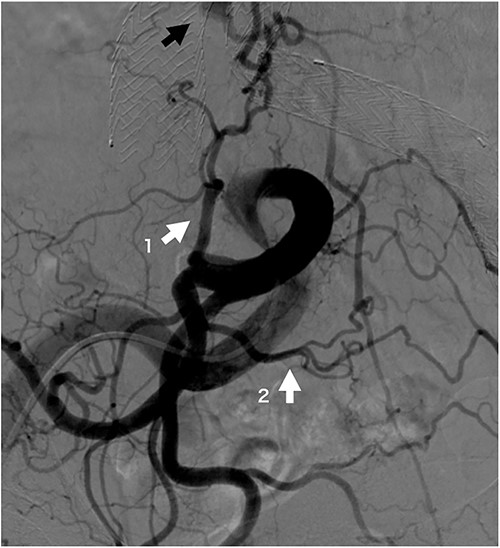

Four patients required reinterventions during follow-up, with one patient presenting with a Type Ia endoleak and undergoing open surgery at 33 months postoperatively, which involved banding of the proximal neck. Another patient was diagnosed with a Type II endoleak from the lumbar artery and underwent coil embolization 6 months postoperatively. After performing an iliac artery angiogram, abundant collateral flow, which included the iliolumbar artery leading to the lumbar artery and subsequently to the sac, was observed (Fig. 2). The third patient underwent distal endograft extension for a Type Ib endoleak at 24 months postoperatively. The last patient underwent aortic angiography and was diagnosed with a Type II endoleak but declined further surgical treatment because of advanced age.

Iliac artery angiogram on opposite side of coil embolization procedure site at 6 months post-operation. The iliolumbar artery (white arrow 1), a branch of the internal iliac artery, and the lateral sacral artery (white arrow 2), a branch of the superior gluteal artery, are well developed and form a rich arcade. The black arrow indicates the sac refilling flow.

In our case of reintervention for Type II endoleaks, the hypogastric artery on the opposite side of the embolization demonstrated abundant blood flow to the median sacral and lumbar arteries. This phenomenon can be attributed to the hypogastric artery route, which involves the contralateral hypogastric artery, lateral sacral artery, and ipsilateral hypogastric artery [14]. An increase in blood flow in the superior gluteal artery, located upstream of the lateral sacral artery, results in augmented flow to its branch (i.e. the median sacral artery) that then drains into the sac. This increased blood flow is a Type II endoleak, validating our hypothesis.